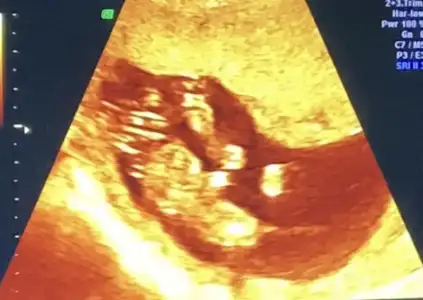

Merhaba yeni uyeyim elimde 7 haftalik karindan 10 haftalik alltan ulturason goruntusu var cinsiyet tahmini yapabilirmisiniz acaba şimdiden teşekkurler ilk resim 7 hafta karin son resim 10 haftta altan bakildi.

Banada bakarmısınız şimdi ikili testten çıktım doktor erken dedi soylemedi çok merak ediyorum 12 haftalik

Merhabalar, ctesi ikili test icin gittim 11+6 idim. Suana kadar hep haftayla uyumlu giderdi sat. Ama bu sefer 12+6 cıktım. Yine de cinsiyet yorumlar mısınız? Gec mi kaldım? Bir de doktor tahminini söyledi ama emin değil. Kafanız karışmasın diye en son söyleyeceğim.

Bir de bunu verdi doktor. Sanırım bacak arası ve kenardakiler de bacakları burada. 11+6 idim.